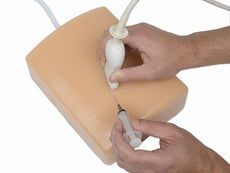

Brand New! 2nd Generation upper torso ultrasound guided central line placement training model with transparent tissue insert allows users to develop and practice the skills necessary to gain proficiency in using ultrasound to guide central catheter insertions in the internal jugular vein (IJ), subclavian vein, and axillary vein while revealing the venous and arterial vessels as well as accessory boney structures. Developed with the goal of helping clinicians bridge the learning gap by allowing them to see the internal anatomical structures with their eyes as well as with ultrasound imaging, our transparent central line placement tissue offers superb ultrasound hands-on training. Using Blue Phantom proprietary simulated human tissue, this very realistic and ultra-durable transparent central venous access ultrasound training model is excellent for training clinicians in the psychomotor skills associated with ultrasound guided central line placement procedures. These ultrasound imaging skills include; using ultrasound system controls, transducer positioning and movement, recognition of arterial and venous anatomy, using ultrasound to target the appropriate vessels for cannulation, and performing a central venous access procedure.Helps

clinicians bridge the learning gap by allowing them to see the internal anatomical structures with their eyes as

well as with ultrasound imaging.

- Developed with the goal of helping clinicians bridge the learning gap by allowing them to see the internal anatomical structures with their eyes as well as with ultrasound imaging

- Developed with the goal of helping clinicians bridge the learning gap by allowing them to see the internal anatomical structures with their eyes as well as with ultrasound imaging